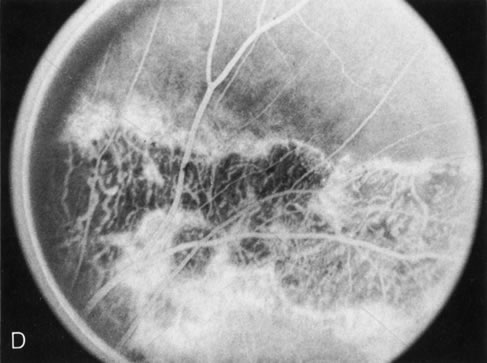

The most common disorder in this group is familial exudative vitreoretinopathy (FEVR), which clinically resembles retinopathy of prematurity, although it is dominantly inherited and unassociated with prematurity or perinatal supplemental oxygen therapy. The mildest changes, documented by FA, are similar to those of the retinopathy of prematurity, namely peripheral retinal capillary nonperfusion and arteriovenous anastomoses. In family members at risk who have a normal-appearing periphery, FA will reveal abnormalities in affected family members and is therefore a sensitive indicator of disease.15

Perifoveal retinal capillary obliteration16 (which may occur throughout the retina and involve the brain)17 requires FA to define this unusual inherited disorder. Inherited retinal venous beading, reported in two dominant pedigrees,18,19 has focal areas of retinal capillary nonperfusion in the posterior pole associated with retinal capillary leakage and intraretinal neovascularization.